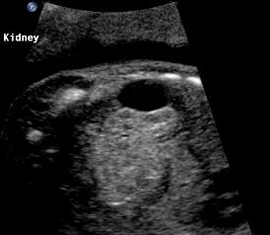

Possible Adrenal Mass

Above. Coronal view. Color Doppler identifies possible mass in region of adrenal gland.

Above. Coronal view. Again, discrete appearing intra-abdominal mass, potentially of adrenal origin.

Above. Longitudinal view. Appearance continues to suggest mass, but follow-up ultrasounds demonstrated resolution of the findings.